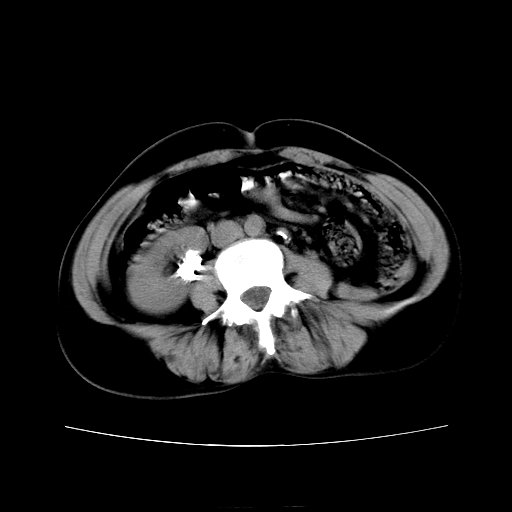

女45y多次(7次)碎石,结果不理想!曾碎石后尿出小碎石,仍腰痛,要求ct,其它不详.本人更倾向于钙化斑!无肾实质破坏,积水等提示集合系统无梗阻.另外腹腔多处钙化.是否结核后改变!谢谢赐教!

1)双肾结石。2)脾脏钙化灶。3)腹膜后多发淋巴结钙化。

尿路结石与腹部淋巴结钙化共存,建议v尿路造影检查,免得钙化灶冤枉为结石受罚。

考虑双肾结石,肾脏实质无破坏表现,没有结核病史,不考虑肾结核,